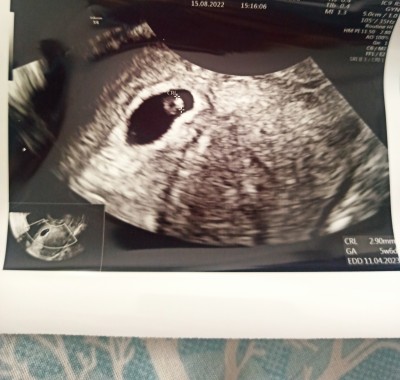

Kese şekline göre cinsiyet?

5+6

kese benimki gibi dik duruyor biraz sadece benimki geniş seninki dar benim kızım olucak senin erkek olcak gibi sanki

İlk çocuğum olacak sağlıklı hayırlı uzun ömürlü bir şekilde gelsin kız erkek fark etmez :) sadece merak benimki :))

Kizin olacak cnm

Kese şeklinin cinsiyet ile alakası yok canım hurafeler bunlar

benim de bu şekil kızım olacak